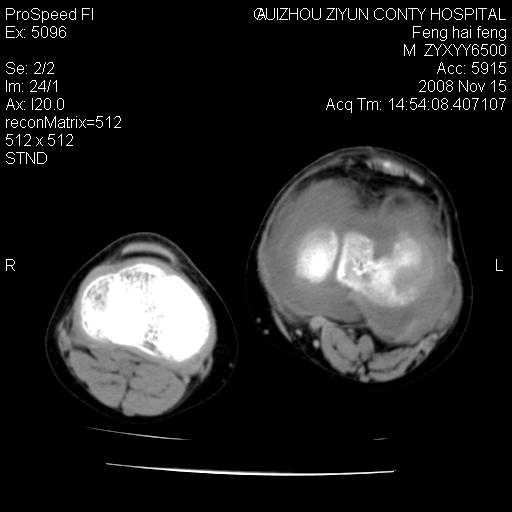

标题: CT16656:M 14Y 左膝关节肿胀一年余。其余病史不详。 [打印本页]

标题: CT16656:M 14Y 左膝关节肿胀一年余。其余病史不详。

考虑左侧髌骨结核;左膝关节滑膜肿胀、增厚,关节囊积液。

左膝滑膜型关节结核可能性大!支持!滑膜型关节结核主要ct表现:关节囊肿胀,积液,关节面见小破坏灶,并见点状死骨!

好大的左腿!考虑左侧髌骨结核,左膝关节滑膜肿胀、增厚,关节囊积液。

左侧髌骨结核;左膝关节滑膜肿胀、增厚,关节囊积液